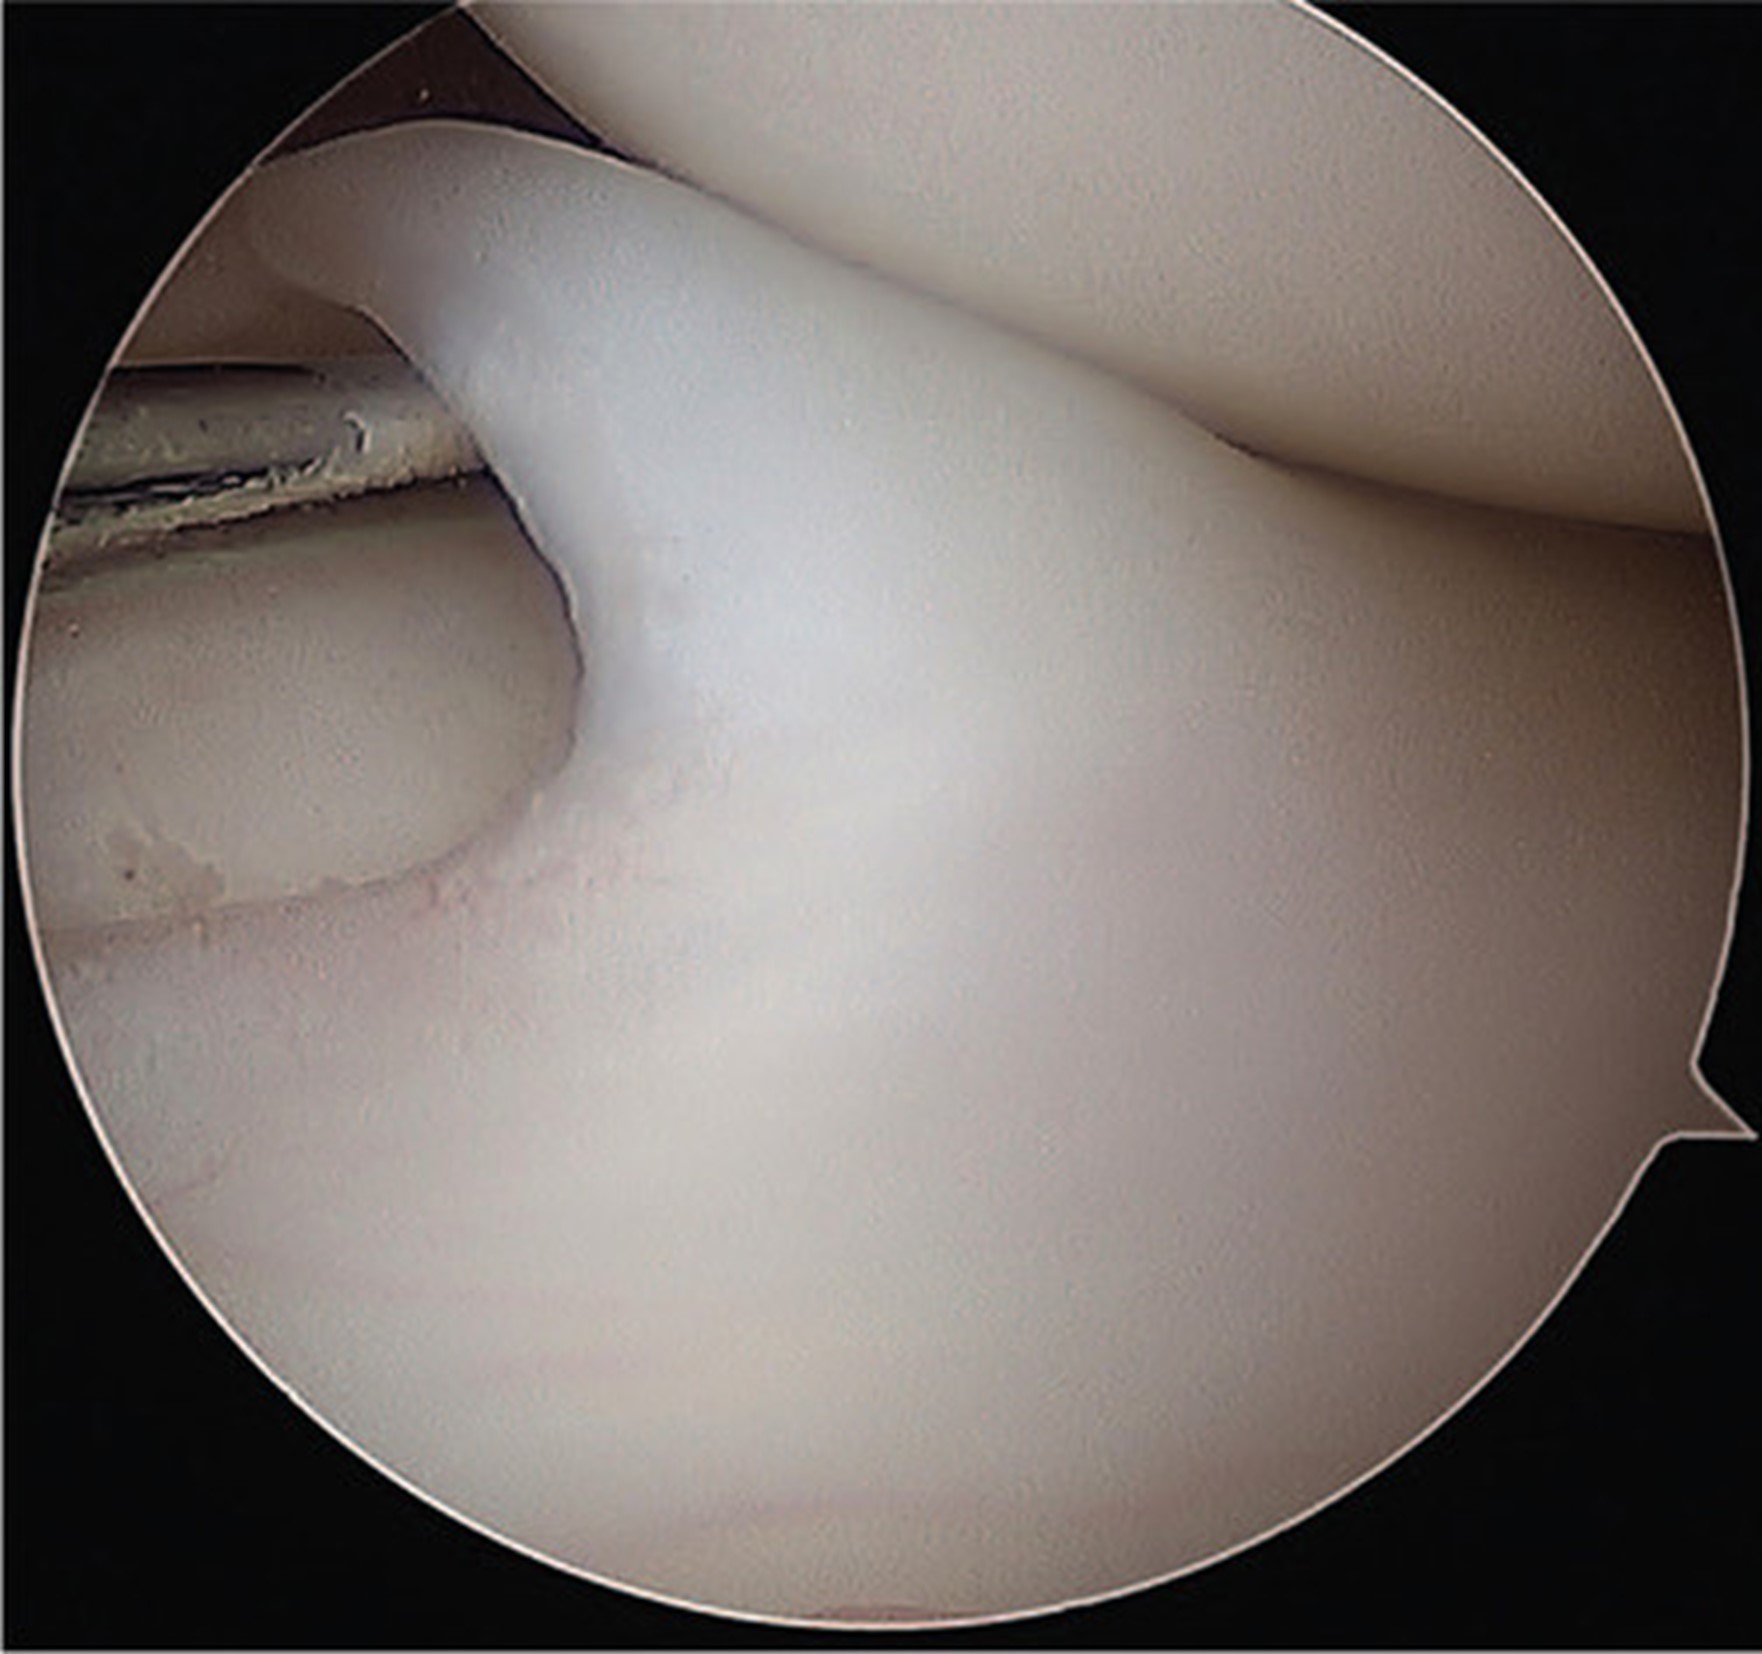

L’esame radiografico può mettere in evidenza segni indiretti della presenza di un menisco discoide, ma l’esame diagnostico di riferimento resta la risonanza magnetica che permette di identificare anche eventuali lesioni a carico del menisco.

ll trattamento chirurgico trova invece indicazione in presenza di una sintomatologia tipica, non responsiva alle terapie conservative. Le opzioni a disposizione vanno dalla saucerizzazione, ossia un rimodellamento del menisco discoide sino ad ottenere una normale morfologia e funzione meniscale, la stabilizzazione periferica associata o meno alla centralizzazione qualora sia presente una problematica di instabilità sino alla riparazione dei diversi pattern lesionali. A prescendere dal tipo di trattamento chirurigico, l’obiettivo è quello di preservare quanto più possibile il tessuto meniscale.